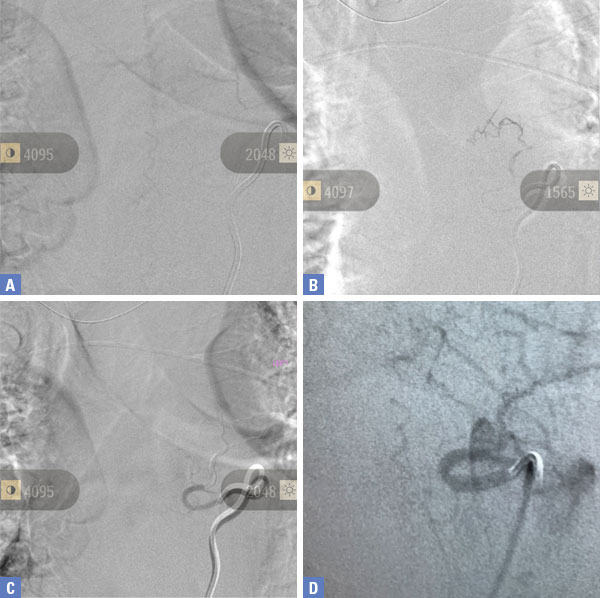

The patient is a 65-year-old woman with a history of hypertension and hypercholesterolemia who was experiencing bilateral lower extremity weakness and numbness for close to one year in addition to some urinary incontinence for the preceding 6 months. The patient ultimately saw a neurologist who ordered an MRI of her lumbar sacral region revealing a bright signal within the lower spinal cord on T2-weighted sequences with enhancement and flow voids seen on the dorsal aspect of the spinal cord suggestive of spinal dural arteriovenous fistula (Figure 1). She was referred for a neurovascular consultation. Physical examination was significant for 4/5 weakness on the right hip and leg muscle groups with decreased pinprick and light touch sensation in both lower extremities in a stocking distribution and decreased vibratory sensation in both toes.

(Figure 1) Pre-treatment MRI image of lumbar sacral region.